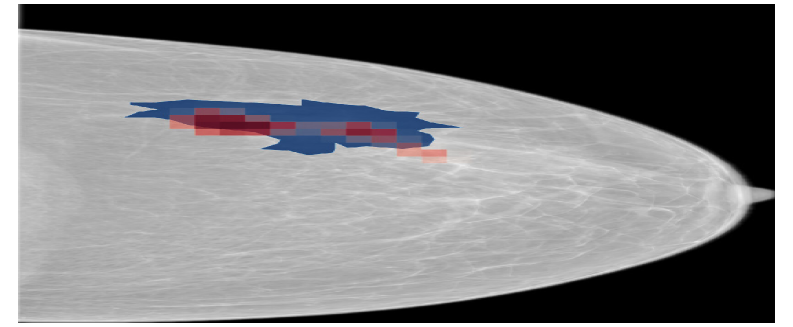

Refer to caption

(a) NYUtr\mathcal{M}_{\mathrm{NYU}}^{\mathrm{tr}}

(b) NYUtr\mathcal{M}_{\mathrm{NYU}}^{\mathrm{{}^{\prime}tr}}

(c) NYUtt\mathcal{M}_{\mathrm{NYU}}^{\mathrm{{}^{\prime}tt}}

Figure 9: Saliency maps generated by NYUtr\mathcal{M}_{\mathrm{NYU}}^{\mathrm{tr}}, NYUtr\mathcal{M}_{\mathrm{NYU}}^{\mathrm{{}^{\prime}tr}}, NYUtt\mathcal{M}_{\mathrm{NYU}}^{\mathrm{{}^{\prime}tt}} models on a sample from the CSAW dataset. Blue regions represent the ground truth annotations, while red regions highlight the saliency maps corresponding to the malignant class.

Saliency maps in Figure 9, generated for a CSAW sample, further support this conclusion at a higher level. While the NYUtr\mathcal{M}_{\mathrm{NYU}}^{\mathrm{tr}} model accurately identified the relevant regions, the model evaluated on the altered input distribution (NYUtr\mathcal{M}_{\mathrm{NYU}}^{\mathrm{{}^{\prime}tr}}) failed to highlight the correct areas. Nevertheless, when test-time BN statistics were applied to the altered input (NYUtt\mathcal{M}_{\mathrm{NYU}}^{\mathrm{{}^{\prime}tt}}), the model’s ability to localize the correct regions was restored.